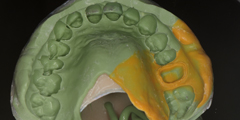

診断用ワックスアップ作成

咬合器付着後に模型上で理想的な咬合関係の構築モデルを作製する事。

技工士-歯科医師-患者様の三者間での具体的ゴールの設定と状況に応じた複数の治療プランの提示可能。